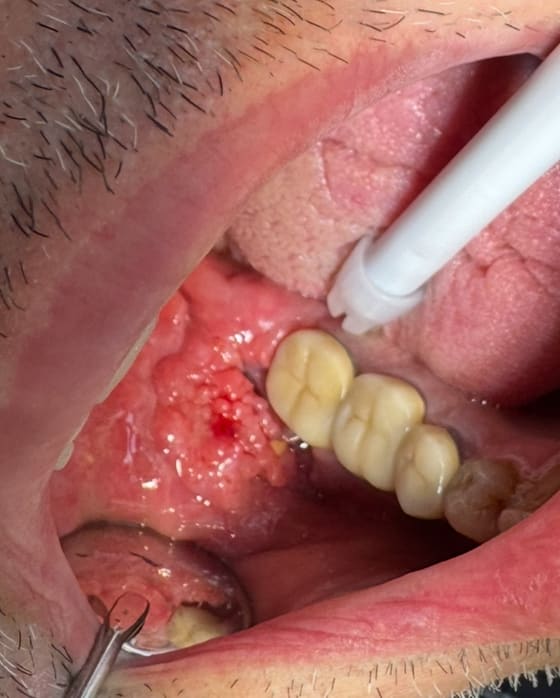

558904719_10163144646272247_6774572045327740986_n.jpg